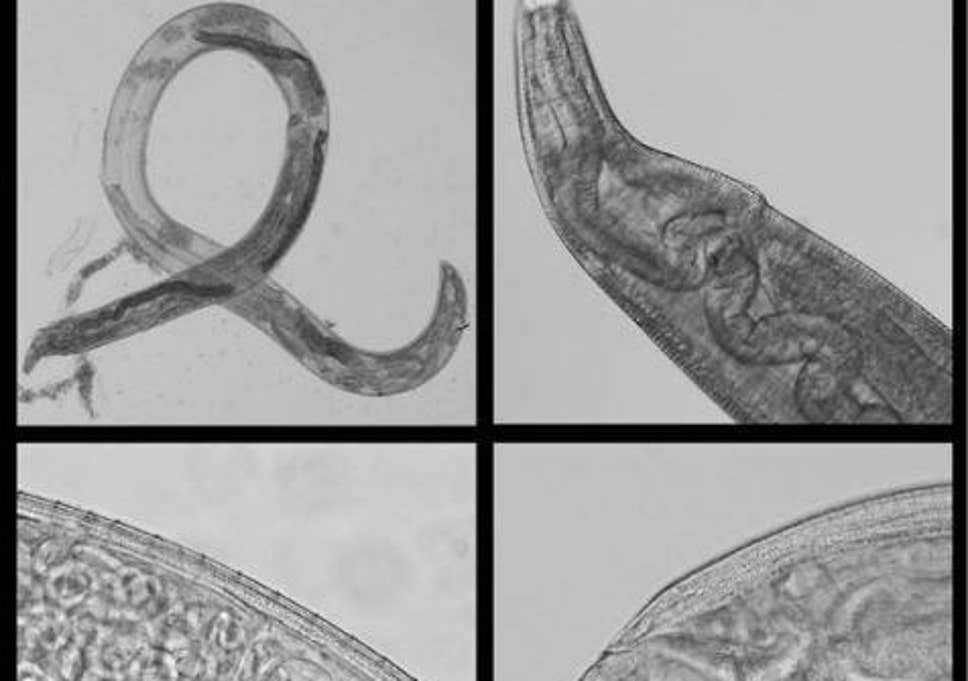

Read MoreStudy says : Lady’s eyes infected with parasitic worms perhaps after experience with swarm of flies while on run

MONTEREY, Calif. – An investigation distributed by the Oxford scholarly diary Clinical Infectious Diseases detailed the second restoratively recorded instance of an uncommon contamination that included a patient’s eyes being transformed into a reproducing ground for parasitic worms. As per Live Science, the 68-year-elderly person was visiting California from their home in Nebraska where they apparently found a roundworm wriggling out of their correct eye when she felt bothering. Subsequent to looking carefully, they in the end found another worm and promptly looked for restorative consideration in Monterey, California, as…